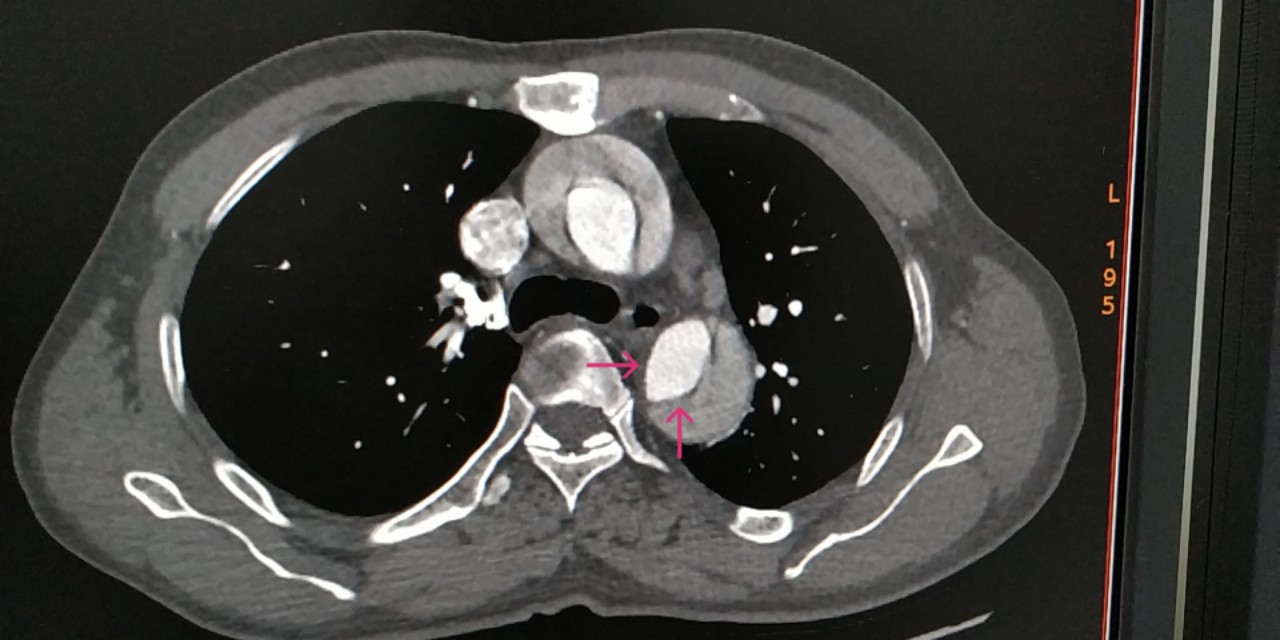

感觉不像,于是带着疑问,跟家属沟通好,我们给患者做了肺动脉和主动脉的全层CTA,发现是那个隐藏已久的杀手——主动脉夹层。而且,是全层撕裂,如下图。

咱们再聊聊主动脉夹层这个病。主动脉夹层是血管撕裂性疾病,指的是人体最大的血管主动脉内膜破裂,血流在经过破口的时候进入中膜,形成真假两腔,类似于双层水杯,类似于轮胎鼓包,这样的一种疾病。死亡风险极其高,多数病人有突发的胸痛,也可以各种症状出现,临床迷惑性极强。

因此,既然是血管内膜的破裂,由于血管的生理保护机制,血小板就会出现聚集进行止血,凝血系统也会被激活参与止血,形成血凝块,只是这种血凝块发生在我们的大血管上,跟我们的手磕破了发生的过程一样。而体内另一个系统——纤溶系统为了对抗凝血也会分解掉一部分血栓变成D-二聚体产生抗凝的效果,只是效果比较弱而已,于是,凝血与血栓分解就这样动态平衡着,直到某一方战胜另一方(出血、凝血、纤溶三者动态平衡相互制约)。